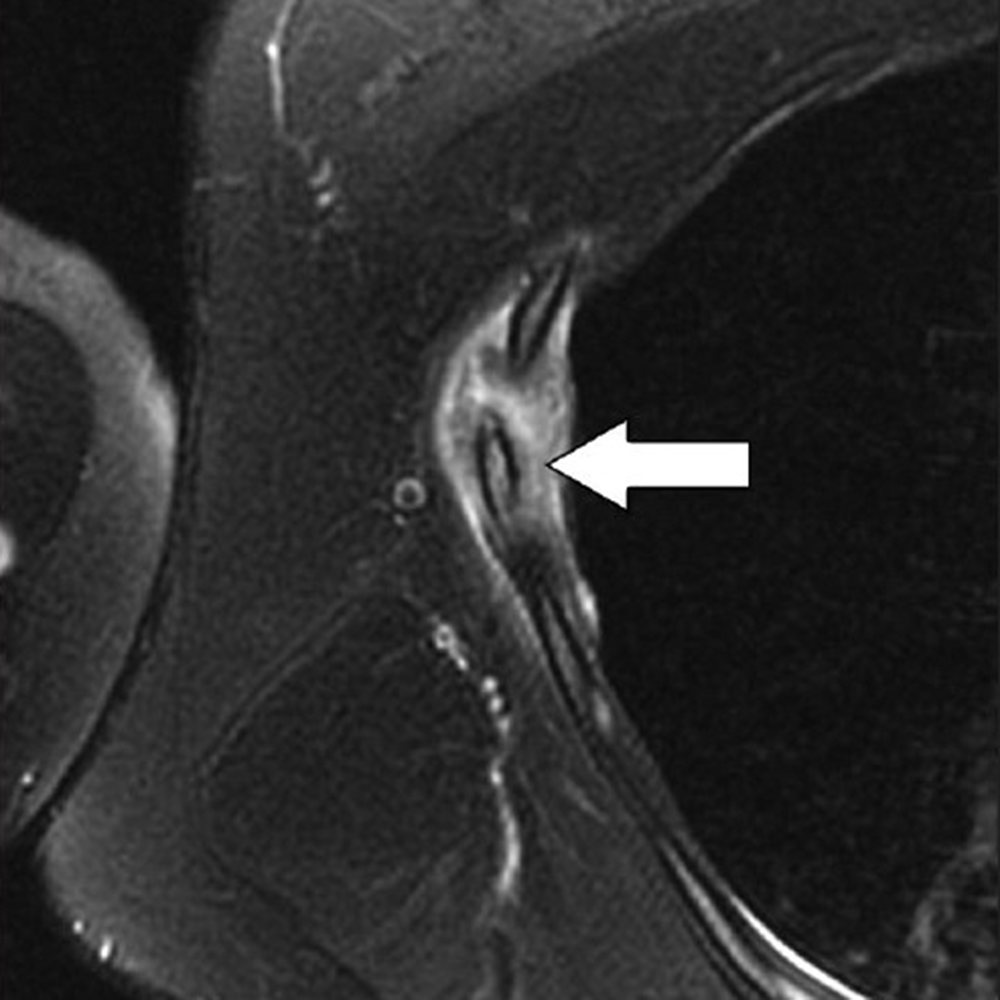

The latter mechanism most often results from strong muscular contraction that is unopposed by a counteracting fatigued muscle. In the case of rib stress fractures, the serratus anterior muscle plays a critical role [3, 4]. The serratus anterior muscle arises from the medial or ventral aspect of the scapula, with multiple slips extending anteriorly that attach to the first through tenth ribs at their middle third. The main role of the serratus anterior muscle is to protract the scapula. Importantly, this action is opposed by the scapular retractors (rhomboid muscles), which stabilize the scapula. In this situation, the serratus anterior muscle will promote an increase in the lateral diameter of the chest cavity. This mechanism can lead to abnormal stress at the middle third of the ribs in sports that involve repetitive contraction of the serratus anterior muscle, such as in elite rowing and swimming. In rowing, stress fractures are relatively common and may affect up to 12% of rowers. The peak contraction of the serratus anterior muscle occurs at the initial phase of the rowing cycle (known as “the catch”), in which the rowing oars are pulled away from the body, causing strong stabilization of the scapula by the rhomboid muscles and serratus anterior muscle. Performed repetitively, this action creates a compressive force vector directed toward the middle thirds of the ribs that can lead to stress fractures, most often affecting the fourth through eighth ribs in up to 86% of cases. If this compression is unopposed by a fatigued serratus anterior muscle, a repetitive stress injury may occur [3, 4]. Stress fractures also affect novice golfers who are still developing their technique and often strike the ground during swing strokes. Frequent ground impact force due to repetitive inaccurate strokes is thought to be transmitted to the chest wall on the leading side, causing stress fractures [5]. Additional sports in which rib stress fractures have been described include baseball, lacrosse, weightlifting, ballet, and gymnastics. MRI findings of rib stress fractures are similar to those seen in the extremities, including a well-defined linear area of low signal intensity surrounded by marrow edema, with the best contrast noted in T2- weighted fat-suppressed images (Fig. 1).

Edema in the surrounding intercostal muscles and extrapleural space is often noted [6]. As mentioned earlier, such fractures may be better depicted on oblique sagittal or coronal images that are tangential to the fracture and provide context, better showing rib portions adjacent to the fracture itself. Healing of rib stress fractures can be monitored by MRI, showing progressive improvement of marrow edema and bony bridging; however, clinical symptoms may persist even though the fracture appears healed on imaging.

MRI provides excellent contrast to show costal cartilage fractures, which will appear as linear areas of high signal intensity against a background of low-signal-intensity costal cartilage [8]. Although MRI has superb spatial resolution and contrast, its relatively higher cost and susceptibility to respiratory motion artifacts decrease its effectiveness, when compared with CT. Ultrasound may also prove useful, given the superficial location of costochondral structures, and may show a focal stepoff at the fracture area [1]. As previously mentioned, costal cartilage injuries may occur at the sternochondral or costochondral junctions. At these locations, chondral and adjacent bone marrow edema may be present on MRI and represent the dominant findings related to traumatic injury. Treatment of costal cartilage injuries include NSAIDs, taping and immobilization belts, and rest for 2–3 weeks. In certain situations, such as treatment of professional athletes, pain can be mitigated by local injections of anesthetic [8]. An important differential diagnosis to consider when entertaining the possibility of a costochondral injury is Tietze syndrome. In this rare entity, inflammation of the sternochondral junction (the most common symptom) can occur spontaneously and lead to focal pain without any specific initiating event. The cause of Tietze syndrome is uncertain, and the condition usually affects younger patients (< 40 years old). On MRI, this entity may show edematous change surrounding the sternochondral junction, which is best seen on fat-suppressed T2-weighted images [10]. CT may not provide enough tissue contrast for adequate detection. Given that Tietze syndrome is usually self-limited, its treatment includes rest, NSAIDs, and local anesthetic injections in refractory cases.